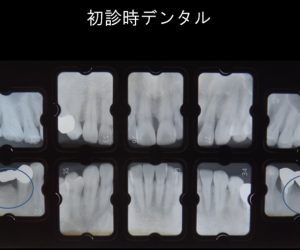

1本の歯も抜かず保存出来ている症例

投稿日:2019年3月18日

この症例は重症の歯周病の患者様を1本たりとも歯を抜かず安定している症例です。 歯茎が腫れあがり膿をもっていました。青丸の部分です。全顎的に重度歯周病です。 歯周病のプログラムを当院で受けて頂き特に再生療法の様な手術もせず […]